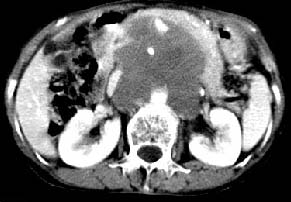

我的第1诊断还是考虑是淋巴类病变1}。从病灶形态上看不是很规则,但其更向是多个结节的融和,其内有少许坏死,整个病灶的强化不是很明显,临近左恻肠间隔有增厚,2}我认为更重要的一点的是肠系膜有明显增厚呈片状。3}患者的脾脏不大其未见异常病灶。结合以上几点我首先考虑是转移性{但对此诊断我觉得不足之处;转移性的淋巴结肿大融合为什么没有坏死?}。{另外患者无大便习惯改变及血便,其发现右颈包块在今年过年无意发现}。以上是我的浅分析望各位战友继续讨论!谢谢!!

实话实说,不认识,看什么都象!!我怎么感觉左侧肠管分布及形态那么不舒服呀?病史也有些短,会不会是腹膜后脓肿呀!不好意思,猜的,向大家学习来了!呵呵

讨论:首先看肠系膜和腹膜后的肿块我认为是多发融合的肿大的淋巴结。理由1大小不等的分叶,分布比较

自由。2其中的包绕的血管和周围少量的脂肪即所说的。

同时胃的影象表现和临床的不典型表现,所以我认为淋巴瘤,临床表现不支持胃癌